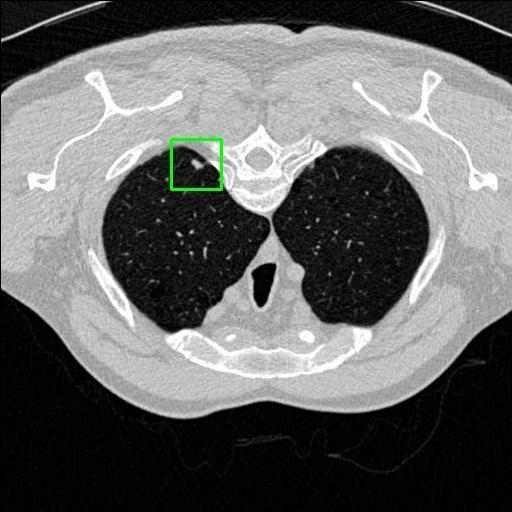

We developed an AI-based system using deep learning models for analyzing lung CT scans to detect and classify pulmonary nodules. We chose the YOLOv11 architecture for its enhanced object detection capability and adapted it specifically for medical imaging, incorporating pixel-level precision and severity classification.

Classification into three severity levels with colored bounding boxes.

Designed a severity classification system that categorizes nodules into null, moderate, and severe using colored bounding boxes, assisting in rapid clinical decision-making.